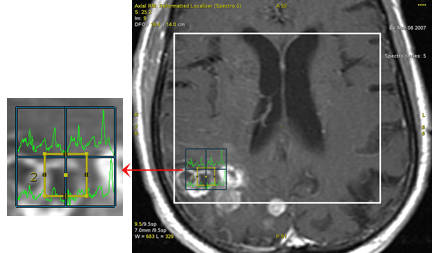

Position the ROI within the spectroscopy voxels.

The corresponding graph reflects the actual position and size of the ROI within the area of the highlighted spectroscopy voxels.

The graph curve represents the weighted average of the voxels in proportion of the percentage of their area that is within the ROI boundary.

Table 1. 2D ROI positioned on spectroscopy image

2D ROI position

Corresponding graph